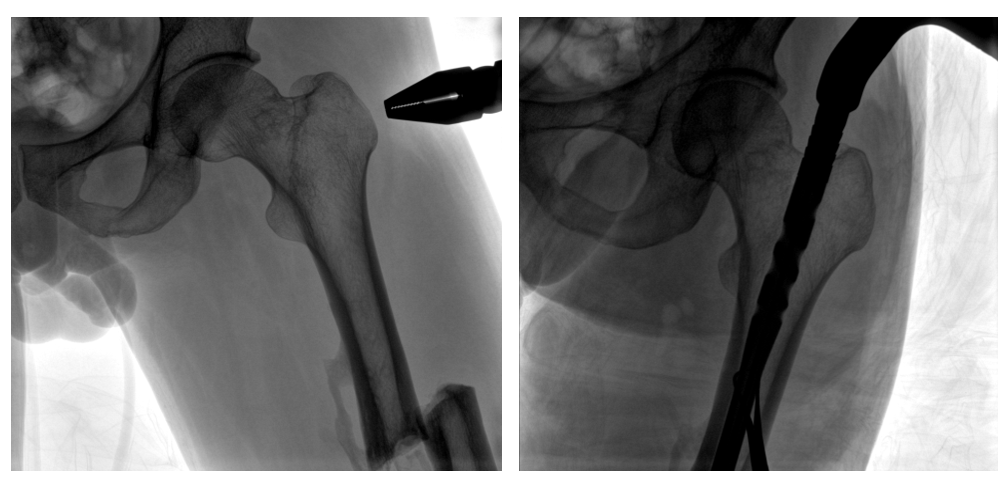

普愛(ài)醫(yī)療PLX119C大平板一體式C形臂采用30CM×30CM的平板探測(cè)器,在脊柱和長(zhǎng)骨骨折等骨科手術(shù)治療中,獲取更大視野、更清晰的骨折部位圖像,能夠有助于醫(yī)生在術(shù)中及時(shí)了解和評(píng)估骨折部位的對(duì)位、對(duì)線情況,且能進(jìn)行長(zhǎng)度和角度測(cè)量,為進(jìn)一步提高手術(shù)質(zhì)量提供強(qiáng)有力的支持。